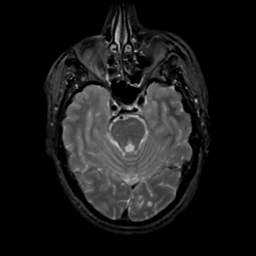

MR Study #16, June 23, 1991 -- Slice #16